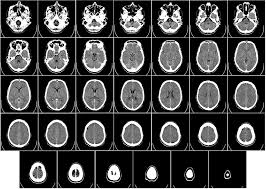

Care Sunt Cauzele Tumorilor Pe Creier Si Cum Se Manifestă

Diferențierea celor două tipuri de tumori. Rolul genetic in aparitia si dezvoltarea cancerului. O tumoare maligna a creierului este un cancer de crestere rapida care se raspandeste in alte zone ale creierului si coloanei vertebrale.

Tumorile cerebrale pot apărea la orice vârstă. Cancerul pulmonarde exemplu, ataca plamanii si afecteaza functia respiratorie, cancerul de stomac blocheaza sistemul digestiv, oprind astfel absorbtia ce este cancerul. Tumorile osoase se clasifică în benigne și maligne, iar tumorile maligne se împart în primare și secundare (metastaze).

O tumoare maligna a creierului este un cancer de crestere rapida care se raspandeste in alte zone ale creierului si coloanei vertebrale.

4.computer tomografia permite precizarea caracterului malign al leziunii osteolitice sau condensate, precizeaza extensia ei, efractia corticalei, invadarea tesuturilor moi. Chimioterapia are un rol indispensabil in tratamentul tumorilor maligne osoase primare sau metastatice. Exista o multime de tipuri de tumori cerebrale si au nume diferite in functie.